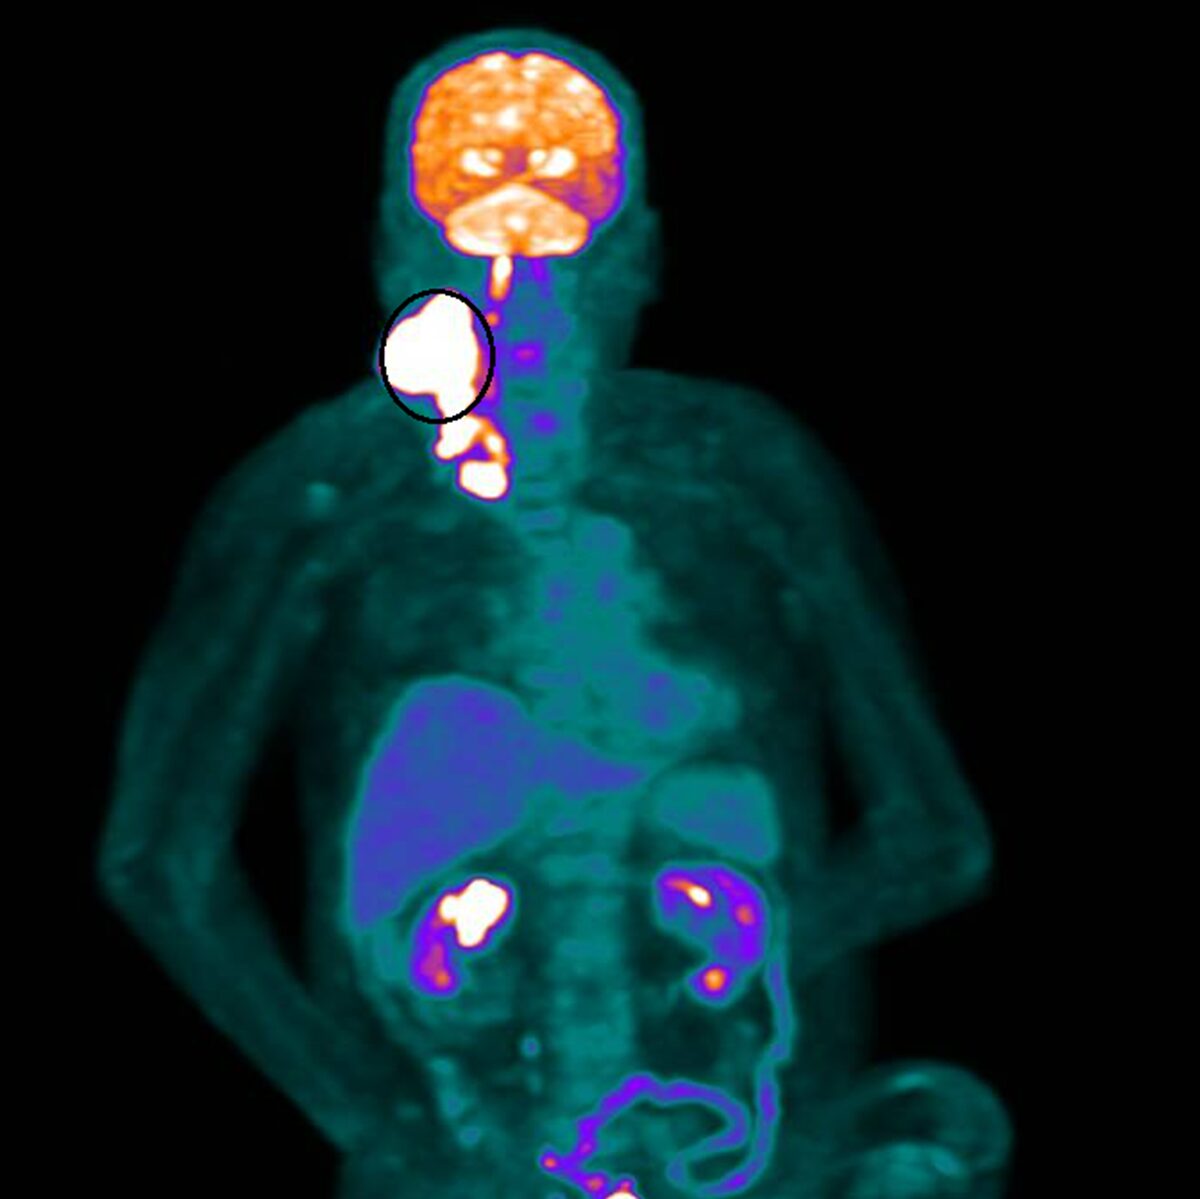

▲醫師張博竣說,林先生隨即展開為期兩個月、共35次俗稱「電療」的放射線治療。(圖/彰化醫院提供)

林先生隨即展開為期兩個月、共35次俗稱「電療」的放射線治療。療程結束後,原本巨大、外觀明顯的腫瘤幾乎完全消失,治療反應遠超預期。這個結果,不僅讓醫療團隊振奮,也為家屬帶來久違的笑容。